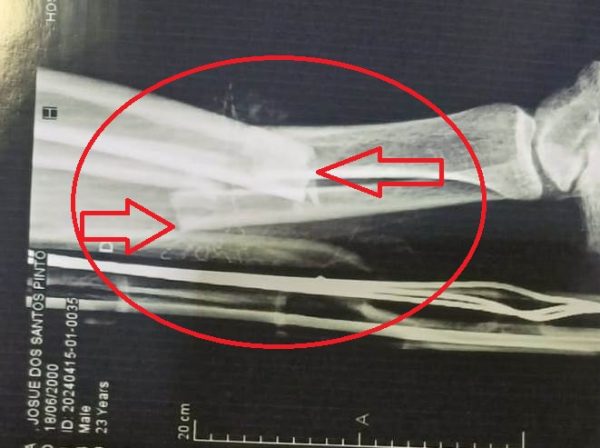

No impacto, o motociclista, que trabalha na Móveis Gazin da Avenida Melvin Jones, sofreu fratura exposta na perna direita. Ele foi socorrido e encaminhado ao pronto-socorro do Hospital Regional pelo Corpo de Bombeiros.